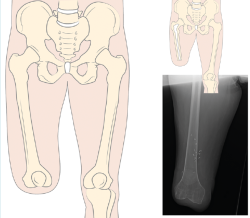

Los criterios de inclusión del estudio fueron: longitud del fémur amputado de al menos 15 cm medidos desde el trocánter mayor, uso de la prótesis convencional durante al menos un año antes del reclutamiento y más de 6 horas de uso del encaje al día, capacidad para andar por interiores y/o exteriores con o sin ayudas, y padecer una amputación TF unilateral. Los criterios de exclusión fueron: presencia de alteraciones cognitivas que no permitieran seguir las instrucciones o las órdenes, peso corporal superior a 100 kg, presencia de patología oncológica o infecciosa activa, infección previa del muñón o longitud del fémur inferior a 15 cm medidos desde el trocánter mayor.